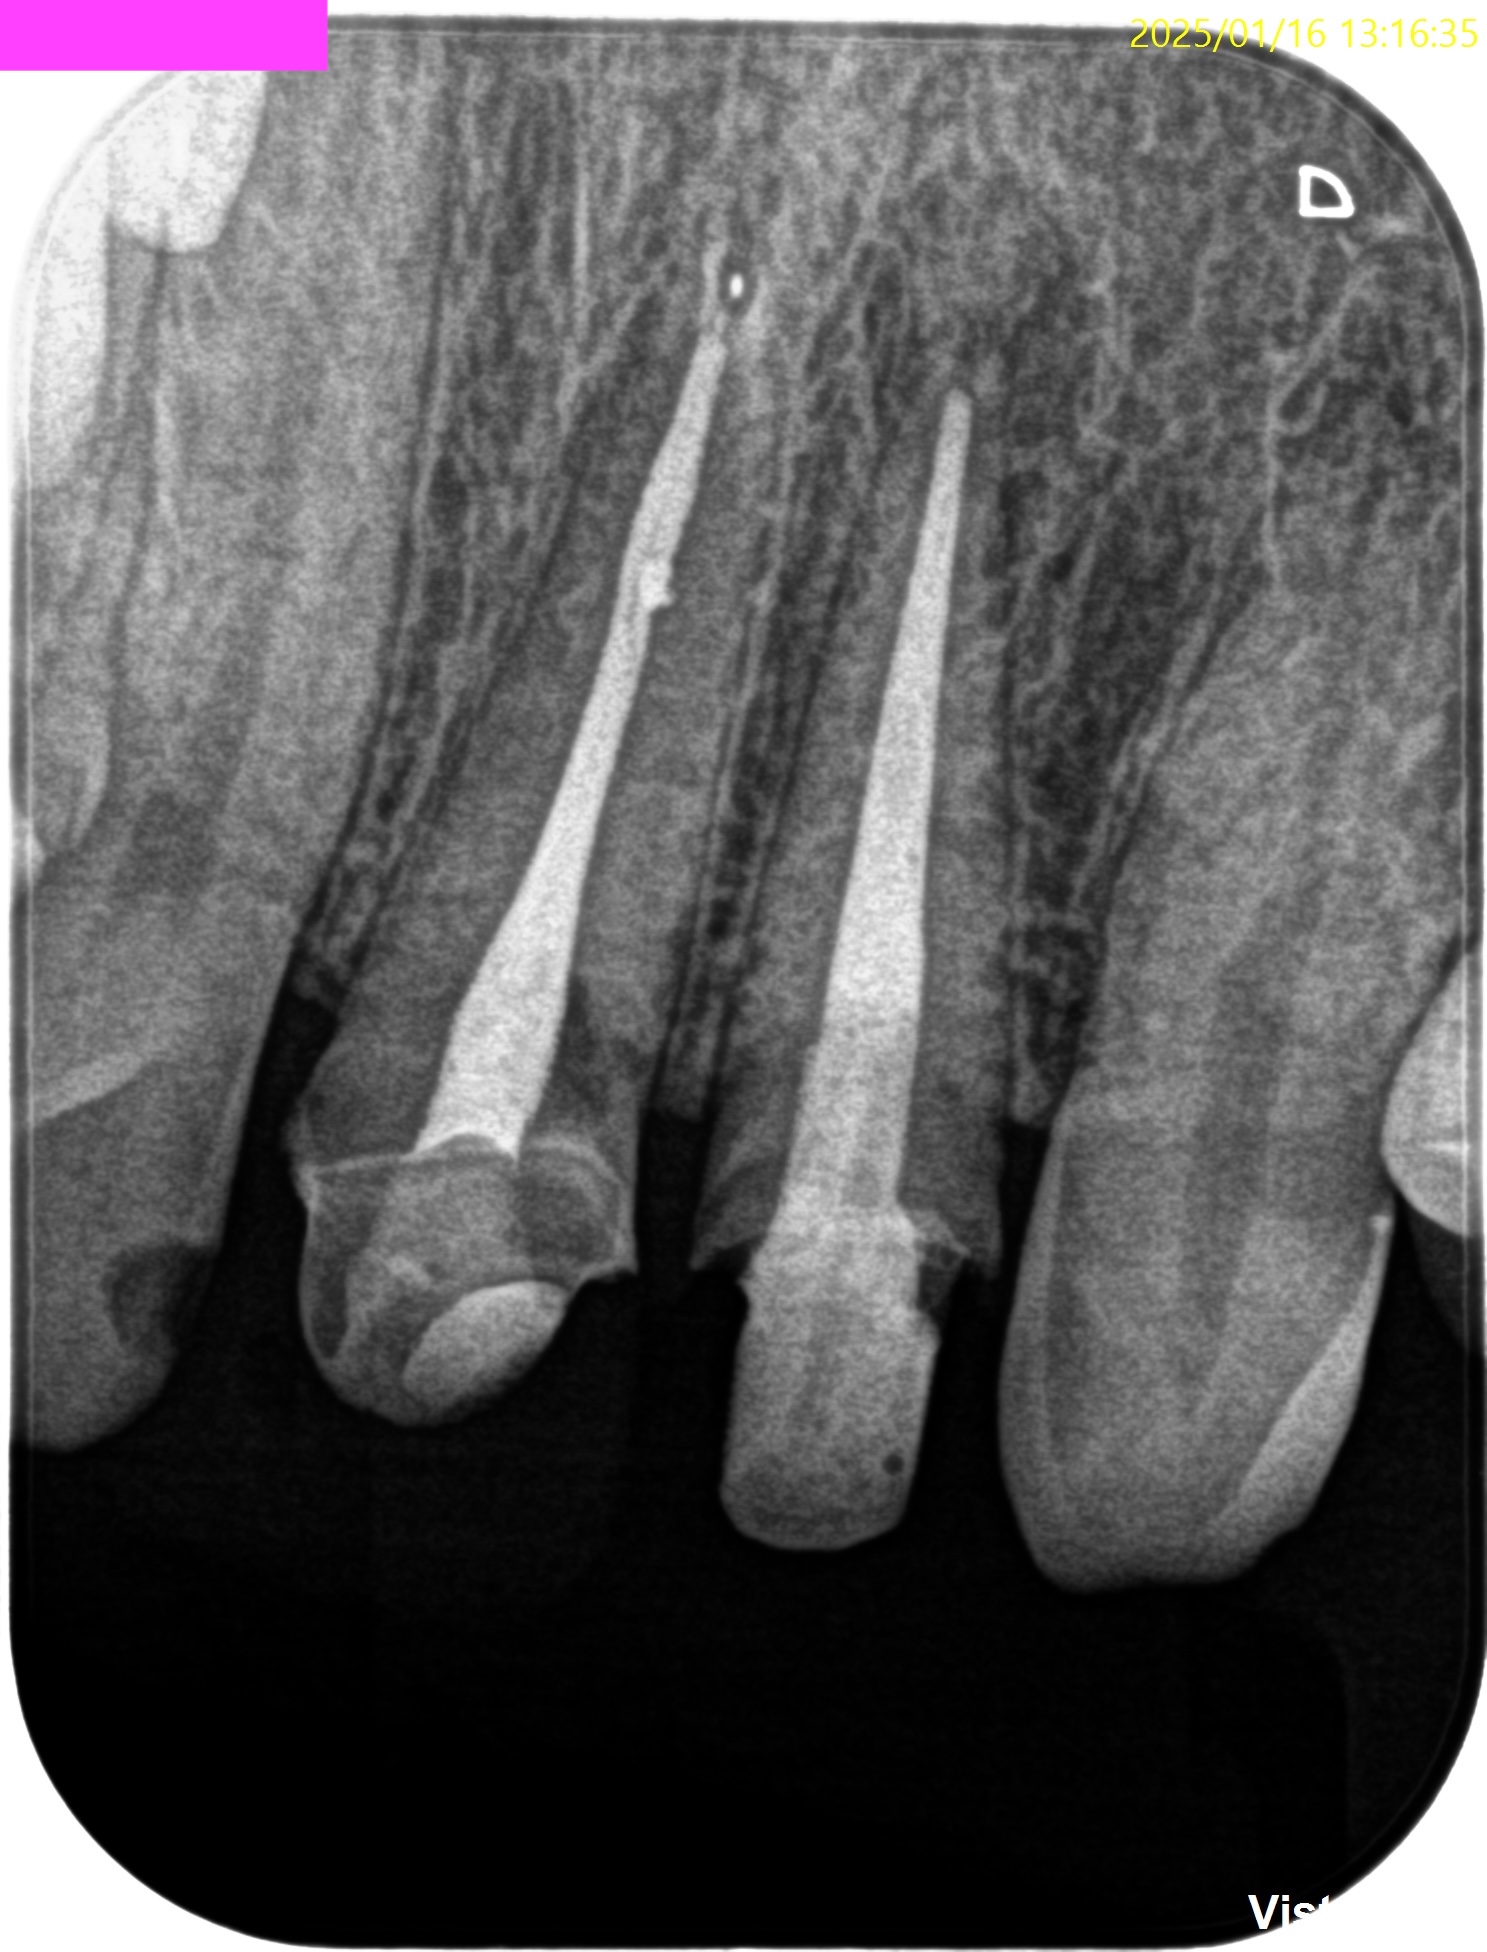

PA(2025.1.16)

#7,10はほぼ治療がなされていない。再根管治療が必要な案件だ。

CBCT(2025.1.16)

#7

頬側皮質骨が消失している。

これが圧痛の原因だろう。

#10

#10も#7に同じである。

根管形成・当該部位への根管充填がほぼなされていないように見えることから, 再根管治療へ移行した。